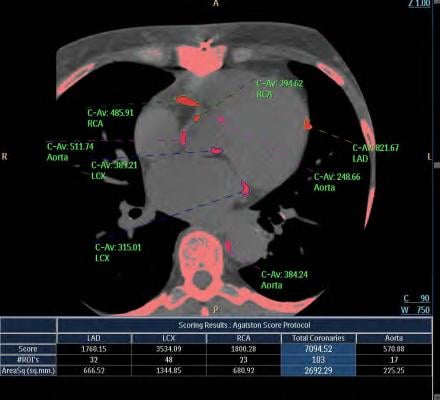

Coronary calcium builds up at the site of coronary plaque, so a CAC scan can be effective in detecting even minute amounts of CAC. The scan results are then recorded using a CAC score, which represents the total amount of CAC in the coronary arteries. The higher the CAC score, the greater the risk for future heart disease.

“There is now sufficient evidence to support the routine use of CAC scanning for screening in clinical practice,” Rozanski said. “Importantly, the CAC score has become one of our most robust predictors of patient risk. Patients are at very low risk when the CAC score is zero and at high risk when the CAC score is highly elevated. Any degree of CAC abnormality, however, even a CAC score of one or above, is sufficient reason for patients to adopt more heart-healthy behaviors.”